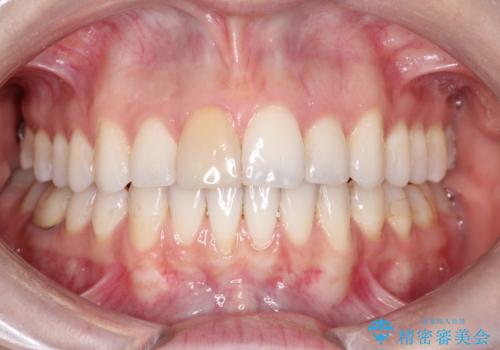

ワイヤーによる抜歯矯正でガタガタと深いかみ合わせの改善